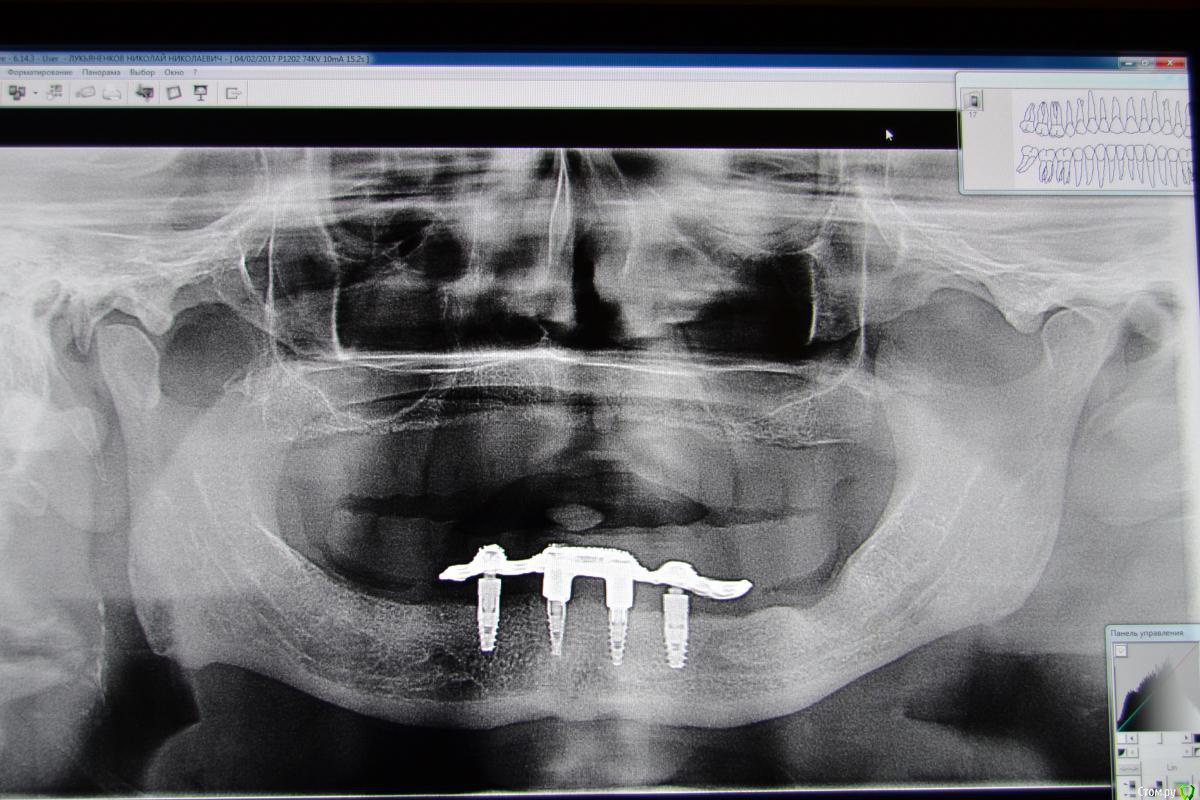

dantist_movani Опубликовано 4 февраля, 2017 Поделиться Опубликовано 4 февраля, 2017 Одна из первых работ. Импланнтаты Niko Leader. Пациент 1949 г.р. Ссылка на комментарий

Rasim-AZ Опубликовано 5 февраля, 2017 Поделиться Опубликовано 5 февраля, 2017 Нельзя было сделать несъемную все на 4х? Ссылка на комментарий

Doc Опубликовано 5 февраля, 2017 Поделиться Опубликовано 5 февраля, 2017 Это не мое решение. Выбор конструкции за техником и ортопедом. Я бы на шариках делалА я бы две балки. Надежно, долговечно, очень хорошо держит и меньше возни с параллельностью.Ну или все на четырех. 1 Ссылка на комментарий

Doc Опубликовано 5 февраля, 2017 Поделиться Опубликовано 5 февраля, 2017 Вот уже десять лет ходит и еще столько же проходит. (В те времена у нас еще не было "все на четырех"). Ссылка на комментарий